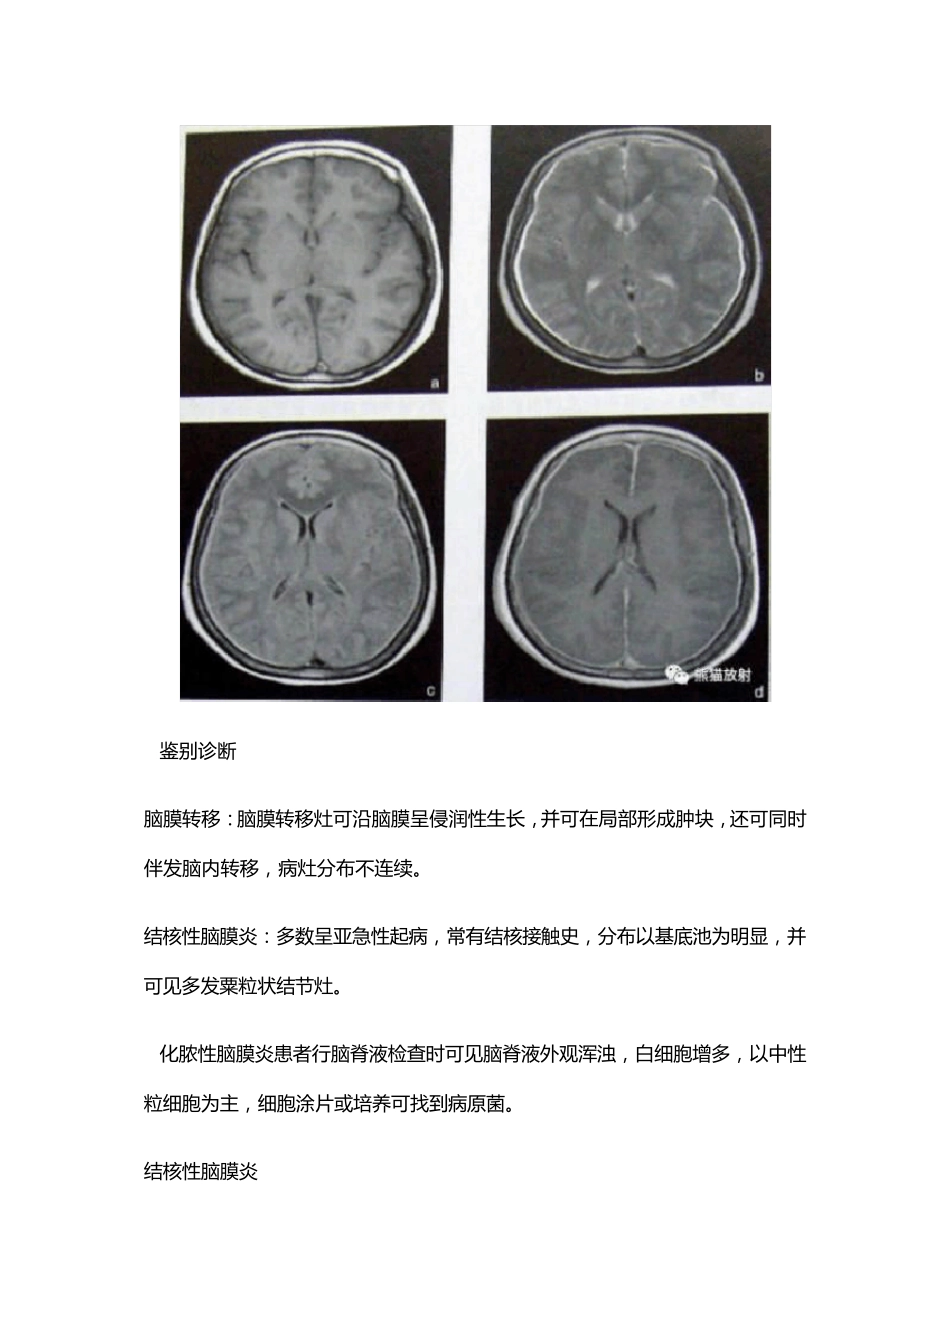

化 脓 性 脑 膜 炎 1.临 床 概 述 化 脓 性 脑 膜 炎 是 常 见 的 中 枢 神 经 系 统 化 脓 菌 感 染 性 疾 病 ,主 要 表 现 为 发 热 、头痛、惊厥和颅内压增高等。 2.CT表 现 平扫可见 基底池和脑 沟的 正常 形态消失, 呈等密度改变, 这是 由于炎 性 渗出物填充脑 池和脑 沟所致;增强扫描可见 脑 膜 强化 ;本病 可并发 脑 积水, CT表 现 为 脑室扩大;本病 可并发 硬膜 下积液, CT表 现 为 脑 外新月形低密度区;本病 并发 脑静脉窦血栓时, 增强扫描可见 典型空三角征, 此征象由强化 的 血流和血管壁与不增强的 血栓共同组成;可并发 出血性 脑 静脉梗死、脑 炎 或脑 脓 肿。 3.鉴 别 诊 断 脑 膜 转 移 : 脑 膜 转 移 灶 可 沿 脑 膜 呈 侵 润 性 生 长 , 并 可 在 局 部 形 成 肿 块 , 还 可 同 时伴 发 脑 内 转 移 , 病 灶 分 布 不 连 续 。 结核性 脑 膜 炎: 多数呈 亚急性 起病 , 常有结核接触史, 分 布 以基底池为明显, 并可 见多发 粟粒状结节灶 。 4.化脓性 脑 膜 炎患者行脑 脊液检查时 可 见脑 脊液外观浑浊, 白细胞增多, 以中性粒细胞为主, 细胞涂片或培养可 找到病 原菌。 结核性 脑 膜 炎 1.临 床 概 述 结 核 性 脑 膜 炎 是 颅 内 结 核 的 最 主 要 表 现 形 式 , 主 要 表 现 为 发 热 、头痛、颅 内 压增高、局灶性 神经功能障碍等症状和体征, 病理主 要 为 脑 膜 增厚和肉芽组织增生。 2.CT表 现 CT平扫可见脑 基底池和外侧裂池密度增高, 增强可见脑 膜 强化;脑 实质内 多个粟粒状结 节灶, 呈等密度, 增强扫描可见病灶强化;本病常见爆米花样营养不良性 钙化, 多位于基底池周围;间接征象包括脑 积水、脑 萎缩和脑 梗死等改变 3.鉴别诊断 脑 膜 转 移 : 脑 膜 转 移 灶 可 沿 脑 膜 呈 侵 润 性 生 长 , 并 可 在 局 部 形 成 肿 块 , 还 可 同 时伴 有 脑 内 转 移 , 病 灶 分 布 不 连 续 。 化 脓 性 脑 膜 炎 : 多 急 性 起 病 , 常 见 脑 积 水 和 硬 膜 下 积 液 改 变 。 4.结 核 性 脑 膜 炎 患 者 行 脑 脊 液 检 查 示 细 胞...